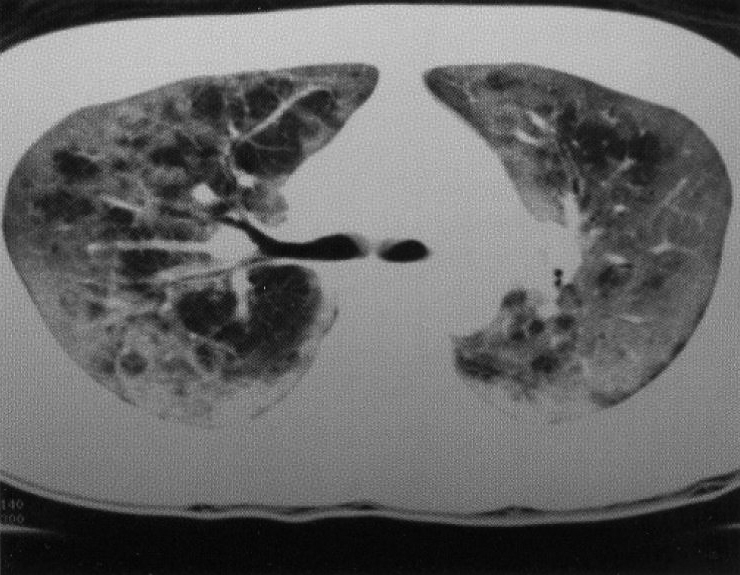

A 25-year old lady worked as a primary school teacher in China and had past history of receiving blood transfusion after wrist cutting as a suicidal attempt. She married to a HK citizen and moved to HK since April 2003. As her husband suffered from schizophrenia and was admitted to TPH psychiatric ward in May 2003, she visited him in the hospital during the SARS epidemic. Then she presented with fever, dry cough, mild dyspnoea and myalgia. Physical examination was unremarkable. Blood results revealed WCC 3.1 x 109/dl, lymphocyte 0.4 x 109/dl, Hb 12.3 g/dl, Plt 127 x 109/dl, LDH 351 U/L. Liver and renal function tests, and clotting profile were normal. Sputum for bacteriological and TB studies were negative. Both corona virus serology and RT-PCR were also negative. Radiologically, there was perihilar hazziness over bilateral lung fields. She was soon started on intravenous hydrocortisone and ribavirin in view of suspected SARS. Initially the fever responded well, but the patient’s oxygen requirement, CXR shadow and lymphopenia deteriorated. Therefore HRCT thorax was performed and showed the presence of pneumatocele on top of diffuse ground glass and consolidative changes (Figure 2). Because of atypical CT finding and clinical course, HIV test was performed and the patient was confirmed positive with CD4 count of 4 only. Sputum examination for PCP came back to be positive. Finally, septrin was started with good clinical response. Upon discharge, she was referred to Kowloon Bay clinic for anti-HIV therapy and antibiotic prophylaxis for opportunistic infection.

Figure 2: HRCT thorax showing diffuse ground glass opacification with pneumatoceles